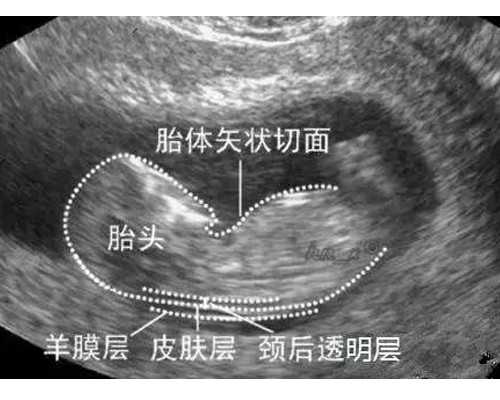

而试管移植失败后刮宫的主要目的在于刺激内膜,这里的刮宫其实属于诊刮,是轻轻的刮一点,这个刮宫叫诊刮,一般内膜厚度可以在B级以上的不用刮,整个过程相当于播种前翻翻土。

试管移植失败后做的诊刮不是清宫手术,一般第一次移植没成功的话,大夫都会建议做宫腔镜,如果内膜不薄的话,会建议刮一层内膜的,刮完就容易着床。

试管移植失败后需不需要刮宫要看具体的情况,一般内膜厚度可以在B级以上的不用刮,这里的刮宫和清宫大有区别,试管移植失败后刮宫的原因在于刺激一下内膜,为下次移植做准备。

试管移植失败后做的刮宫,其实属于诊刮。试管中提到的刮宫其实并不是真正的刮宫,而是轻轻的刮一点,这个刮宫叫诊刮,一般内膜厚度可以在B级以上的不用刮,刮宫可以提高着床率,相当于播种前翻翻土,而且刮出的内膜可以送检。